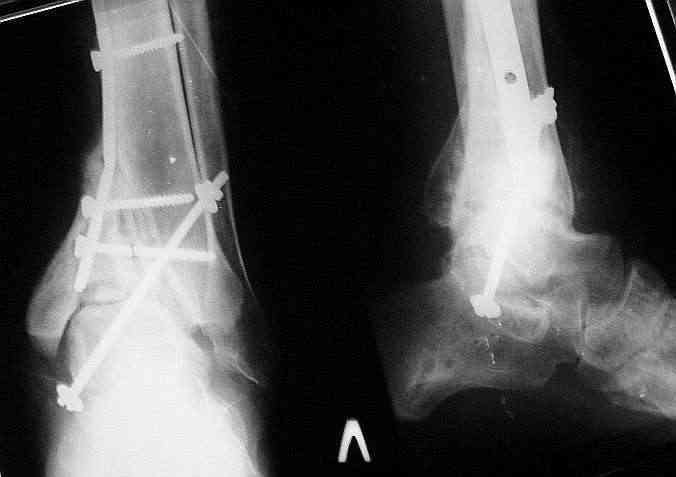

Мной был демонтирован АВФ, удалены все спицы. Больной некоторое время лечился консервативно (шина Белера, антибиотики, перевязки). По заживлению и купировании гнойно-воспалительного процесса была произведена осткрытая репозиция, накостный остеосинтез 1/3 трубчатой пластиной.Такой вариант был принят из-за жуткого остеопороза и отказом больного от предложенного артродезирования голеностопного сустава сразу. Послеоперационный период без особенностей. Через год, больной пришел на осмотр на своих двоих, без дополнительной опоры, с жалобами на боли приходьбе в обл. г/стопа и с желанием замкнуть сустав. В операционной столкнулся с неожиданной проблемой по удалению пластины, она была глубоко вмурована в толщу склерозированного метафиза на глубину 1.5 см; удалить не рискнул (считал, что металл помешает в ходе реконструкции и требуется его удаление).

Было решено, уже по ходу операции, выполнить артродез болтом-стяжкой, тем самым компрессируя резецированные суставные поверхности и смещая стопу латерально, дабы нивелировать варусную деформацию и восстанавливая тем самым опорную ось всей конечности.

Послеоперационный период без особенностей.